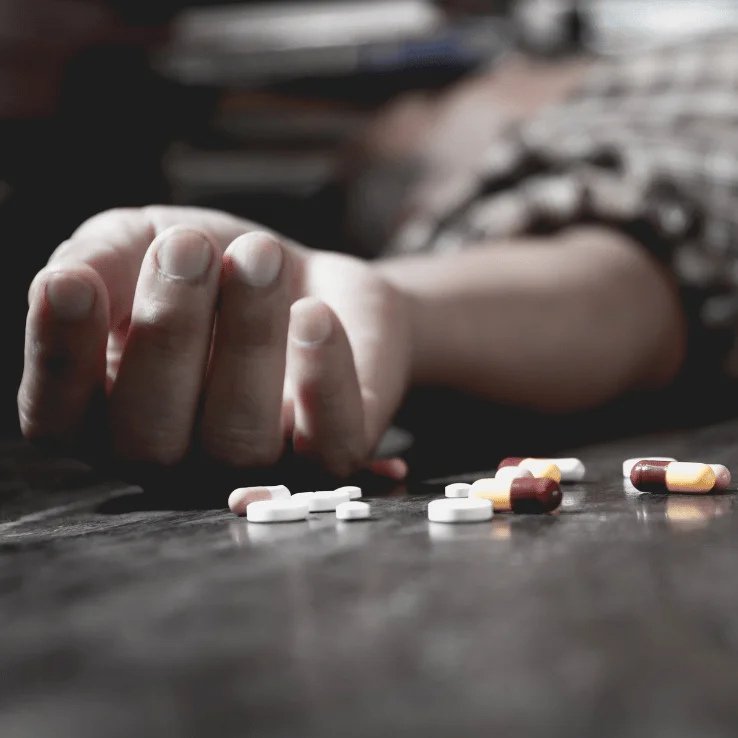

Drug Rehabilitation

Aqsa Charitable Trust is proud to be the only drug rehabilitation center within a 150-200 km radius of Shrivardhan. With 20 beds dedicated to rehabilitation, we will provide a safe and supportive environment for individuals battling addiction. Our rehabilitation program includes medical support, counselling, and therapy aimed at long-term recovery.